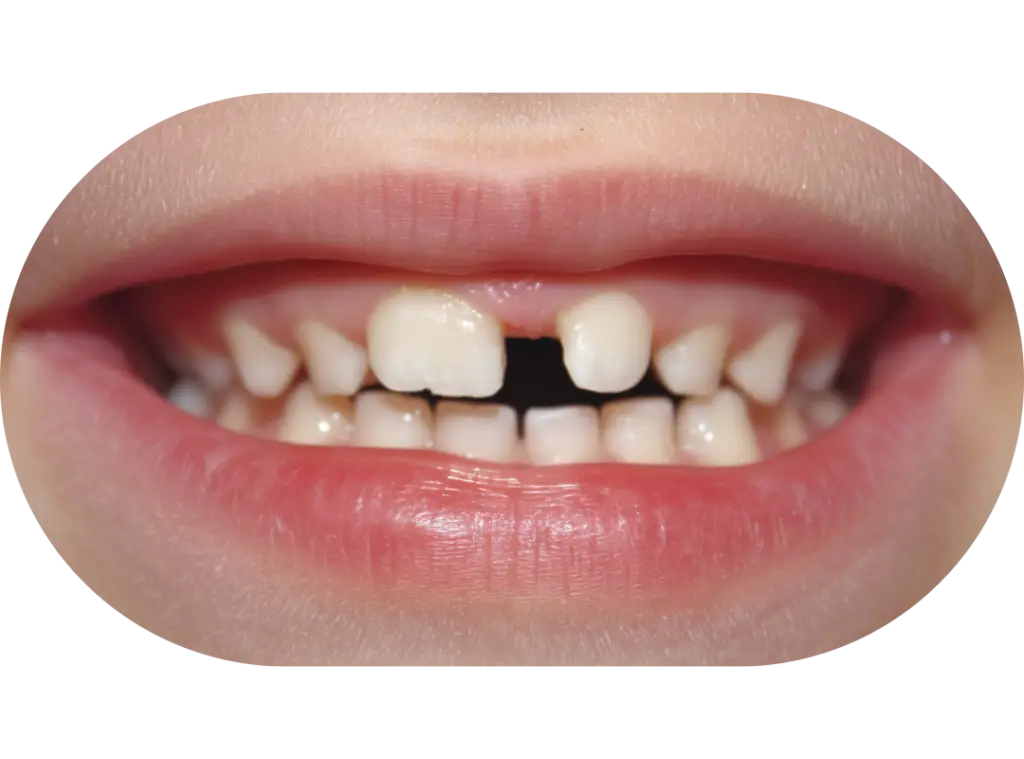

Crowding or Severe Spacing

At this stage, children’s jaws are actively developing and they still have a mix of baby teeth and permanent teeth. Because growth is still occurring, we can guide the jaw and tooth eruption patterns more predictably than we can in later adolescence or adulthood.

Early orthodontic treatment focuses on identifying and addressing orthodontic issues in children, typically between ages 7 and 10.